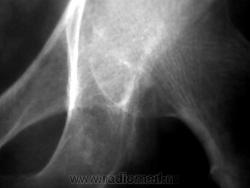

Пациент 48 лет, направлен на R-графию тазобедренного сустава хирургом. Направительный диагноз: коксартороз? При анализе R-граммы, возникли некотрые трудности в её оценке.Какие будут мнения у коллег ?

Извиняюсь, за качество снимка.Трудности вызывает оценка дополнительной тени в форме капли, несколько ниже нижней поверхности головки бедра и кнутри от седалищной кости.